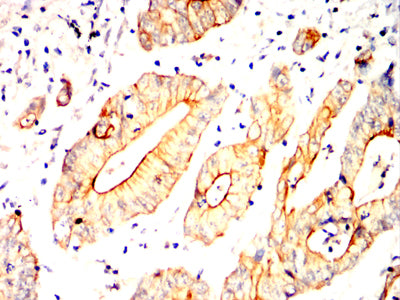

分类: 科研抗体货号: 32358别名: TCF; HNF4; MODY; FRTS4; MODY1; NR2A1; TCF14; HNF4a7; HNF4a8; HNF4a9; NR2A21; TCF-14; HNF4alpha应用: IHC,FCM反应种属: Human

分类: 科研抗体货号: 32343别名: SS1; DRB1; HLA-DRB; HLA-DR1B应用: WB,IHC,FCM反应种属: Human

分类: 科研抗体货号: 32357别名: OCT3; OCT4; OTF3; OTF4; OTF-3; Oct-3; Oct-4应用: IHC,FCM反应种属: Human